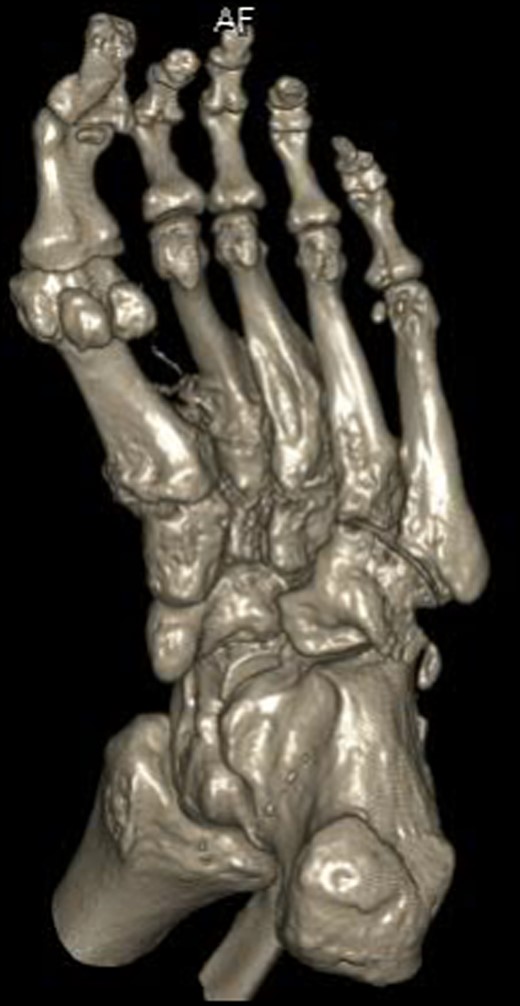

Dorsoplanter, lateral and oblique radiographs demonstrated an additional bone immediately distal to the middle cuneiform articulating with the second metatarsal base and middle cuneiform. Second and third metatarsals were shorßt in comparison with normal (Figs 1–3). Osteoarthritis was seen in all TMTJs and the first MTPJ. A computed tomography (CT) scan confirmed the presence of the additional bone and degenerative joint disease (Figs 4 and 5).

Three-dimensional CT reconstruction of the left foot in the planterdorsal orientation.

The additional bone of this patients foot appears to exist as a completely separate entity to the regular middle cuneiform proximally and the second metatarsal distally. It has developed the characteristic cuneiform wedge shape and size and articulates with the second metatarsal. Given the clinical and radiological conclusions, this extra ossicle represents an interesting finding of a potential additional middle cuneiform.